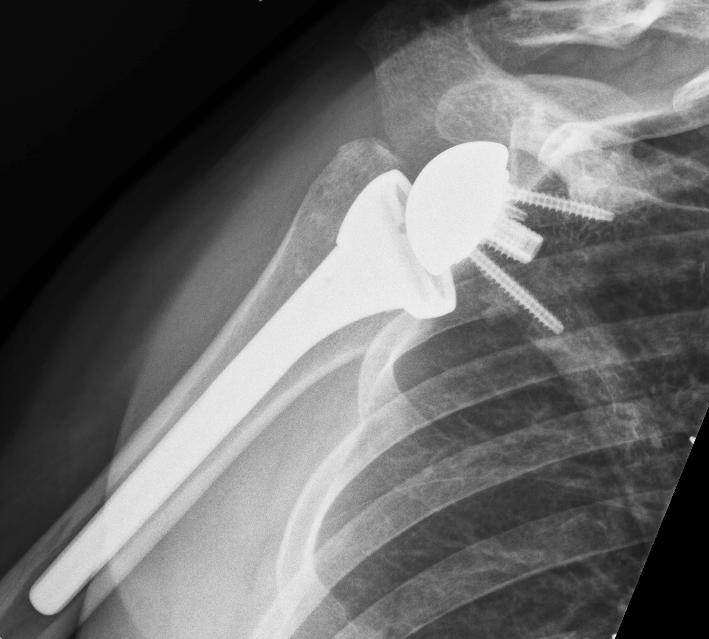

The prosthesis used in a reverse total shoulder replacement is similar to a total shoulder replacement, however the prosthesis is reversed. Instead of the ball on the end of your humerus a socket is placed and instead of the socket on your shoulder blade (glenoid) a ball, or glenosphere, is placed. Hence the socket and the ball are reversed.

At day one postoperatively an xray and CT scan

will be performed to check the position of the prosthesis and physiotherapy will commence. Patients will be in a sling for up to 6 weeks following surgery. The exact time in the sling is determined by the specific details of the surgery. Many patients are only in a sling for a few weeks postop.